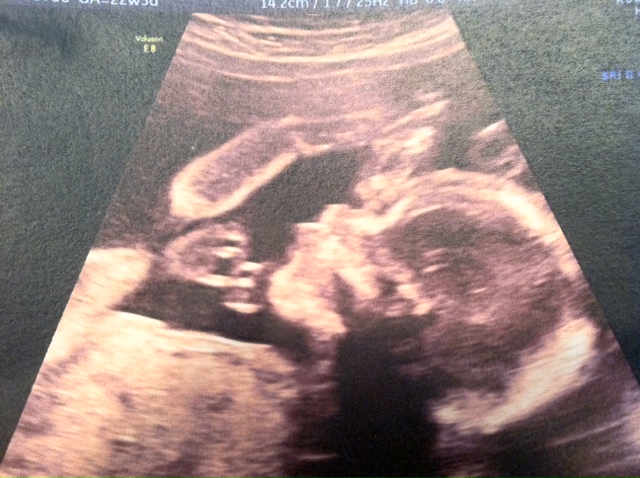

Here are a few of the recent pics (he was being a bit camera shy):